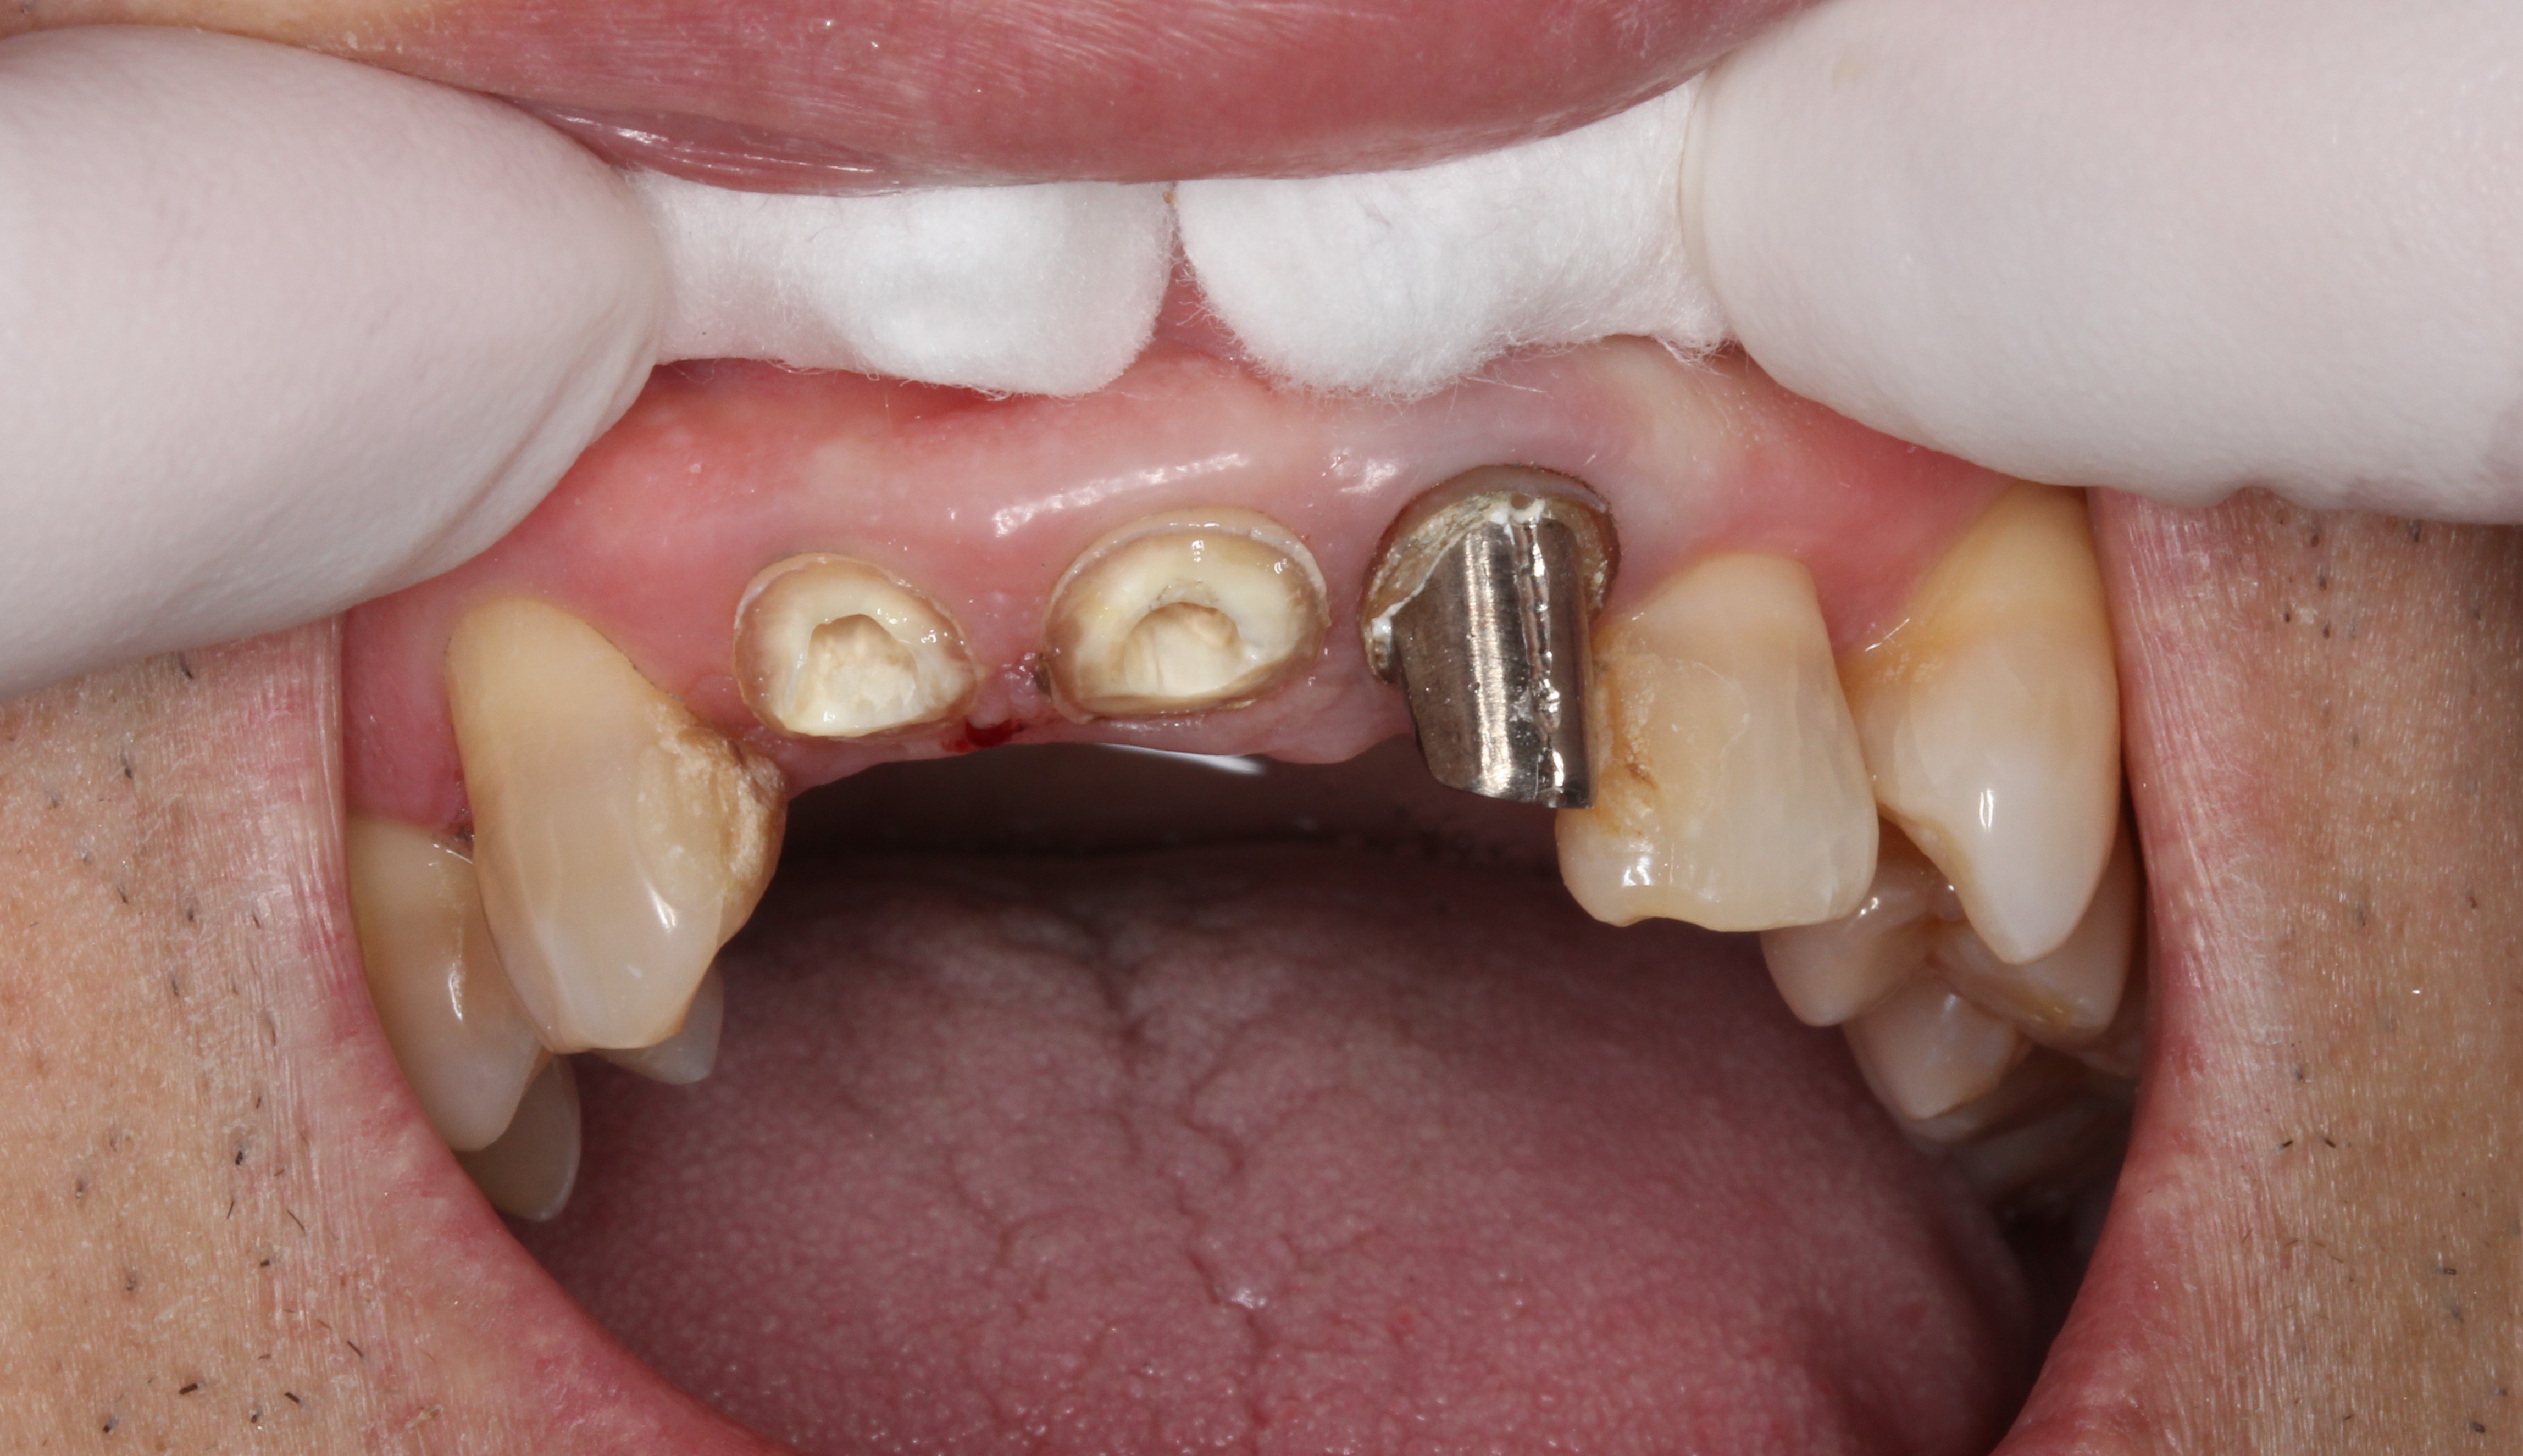

実は外した2本ですが、

歯冠継続歯(ポストクラウン)と呼ばれる、コアと歯が一体型になった差し歯です。歯が割れやすいため現在では保険でも適応外の治療となっています。

1本ずつばらばらに切断していますが、

実際は3本連結し、1本だけは被せ物(クラウン)で、2本は継続歯を全て繋げているという、何とも大変な治療になっていました。

そのおかげで歯が割れなかったのかもしれませんが(-_-;)

それを取るこちらの苦労。

少しでも力のかけ方を間違えると歯が折れます。

技術力が試される高難易度な治療でした。(もうやりたくありません)